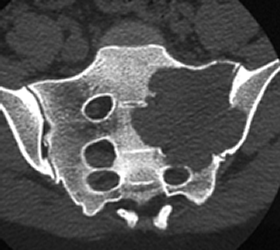

Fig 122. Tumor de células gigantes.

A: Rx lateral, B: RM coronal en T1 y C: RM sagital en T2. Lesión metafisiaria hipointensa en T1 e hiperintensa en T2, que rompe la cortical y forma una seudocápsula hipointensa en ambas secuencias.